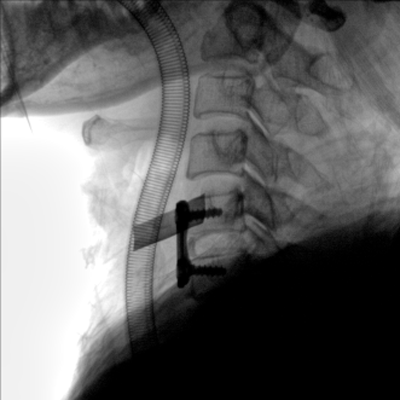

大尺寸動(dòng)態(tài)平板探測器,高DQE、低噪聲、圖像清晰。采用多分辨率圖像增強處理技術(shù),不同部位不同圖像處理算法,滿(mǎn)足客戶(hù)多樣化的需求。

采用智能變頻脈沖透視技術(shù),優(yōu)化圖像質(zhì)量的同時(shí)降低輻射劑量,呵護醫患健康